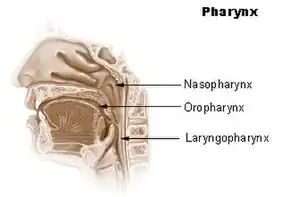

In humans, the pharynx is part of the digestive system and the conducting zone of the respiratory system. (The conducting zone—which also includes the nostrils of the nose, the larynx, trachea, bronchi, and bronchioles—filters, warms, and moistens air and conducts it into the lungs).[1] The human pharynx is conventionally divided into three sections: the nasopharynx, oropharynx, and laryngopharynx (hypopharynx).

Nasopharynx

Oropharynx

Laryngopharynx